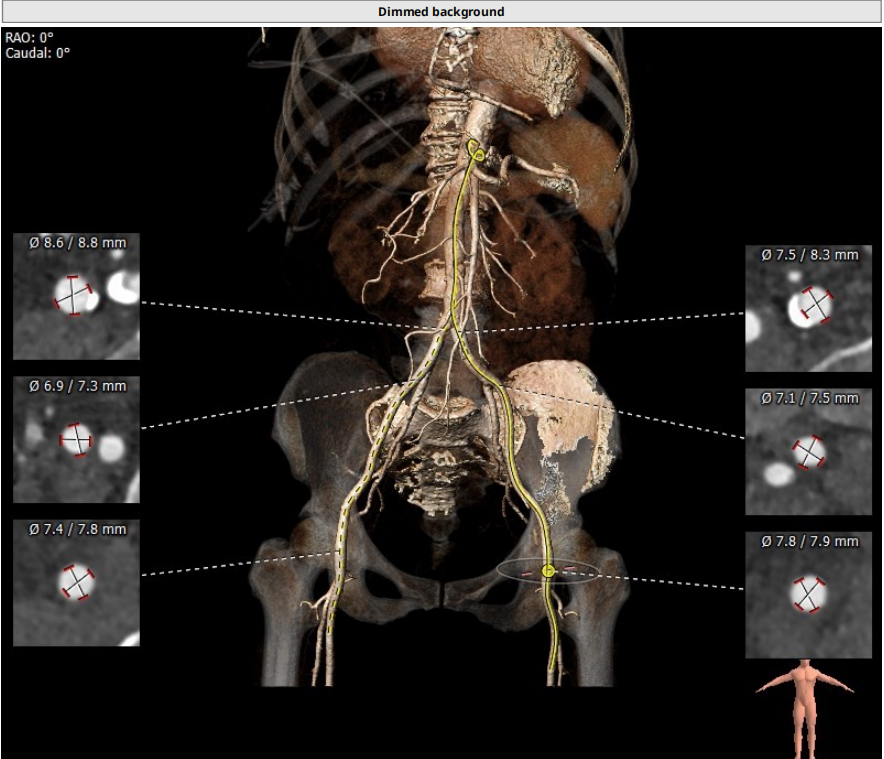

三叶瓣轻度钙化,右无可见钙化脊,瓣叶可见增厚,右冠高度可,左冠开口层面可见瓣叶,升主动脉未见明显扩张,法式窦及窦管交界稍小,两侧股动脉入路可,二尖瓣机械瓣置换术后。瓣环平均径23.7mm,LVOT26.8mm,STJ24.9mm,RCA18.4mm,LCA11.4mm。